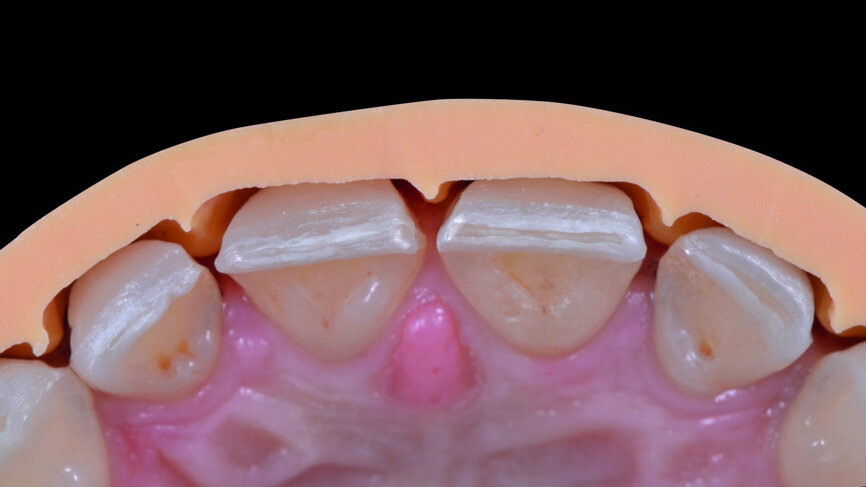

Fig. 9b: Check of the preparation depth, with the use of the silicone guide, palatal aspect.

After six months of tissue stabilisation (Fig. 7), a mock-up was produced with Telio CS C&B (Ivoclar Vivadent) chairside (Figs. 8a & b), and tooth preparations with silicone guides were performed (Figs. 9a–c). Both conventional impressions with polyvinylsiloxane (Fig. 10) and digital impressions (TRIOS, 3Shape) were taken (Fig. 11).